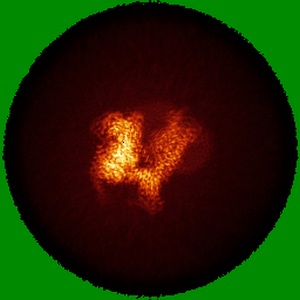

CryoEM structure of mu-opioid receptor - Gi protein complex bound to lofentanil (LFT)

Single-particle3.2 Å

Sample: mu-opioid receptor - Gi protein complex bound to lofentanil (LFT)